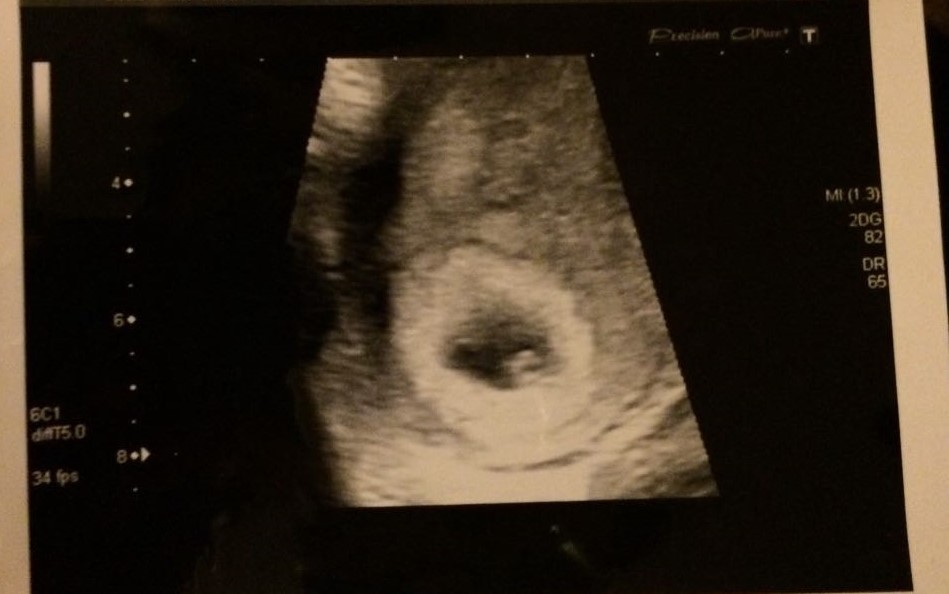

11+2 weeks

Attachment 28532